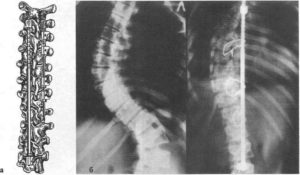

Для уменьшения деформации позвоночника при хирургическом лечении сколиоза и удержания достигнутой коррекции в послеоперационном периоде Райе Р. Э. предложен комплект инструментов и приспособлений. В состав его входят дистракторы различной длины с крючками, временный наружный корректор, щипцы для удержания и установления крючков, щипцы для перемещения верхнего крючка и гаечный ключ.

Дистрактор представляет собой 8-миллиметровый стержень из титана марки ВТ-51 или ВТ-31, в верхнем отделе которого имеются кольцевые проточки, а в нижнем — упор для фиксации каудального крючка.

Крючки имеют боковые отверстия, пред назначенные для установки временного корректора и удержания их специальными щипцами во время операции.

Принцип действия дистрактора основан на возникновении постоянной осевой нагрузки при дистракции, воздействующей на верхний крючок, вследствие чего он наклоняется, прочно фиксируясь на кольцевой проточке стержня дистрактора.

Для перемещения верхнего крючка по стержню имеется инструмент, одна вилка которого упирается на кольцевые проточки, а другая перемещает верхний крючок, вследствие чего возникает дистракционная сила. Крючки имеют различную длину, что облегчает подбор их оптимальных сочетаний в процессе операции.

Отличие предложенного дистрактора от дистрактора Харрингтона состоит в замыкающей системе верхнего крючка на стержне. В конструкции Харрингтона опора верхнего крючка осуществляется на специальный выступ внутри его. Высота крючков Райе Р. Э. меньше высоты кольцевых проточек, и при наклоне опора осуществляется на нижний край крючка.

Кроме того, разная высота расположения при наклоне обеспечивает требуемый угол отхождения их от стержня. Все это облегчает наложение дистрактора в зависимости от анатомических изменений позвоночника при разных локализациях и степенях сколиоза.

С целью использования большого усилия при дистракции и уменьшения возможности образования пролежней в месте соприкосновения металла с костной тканью площадь опоры крючков увеличена в 1,5 раза.